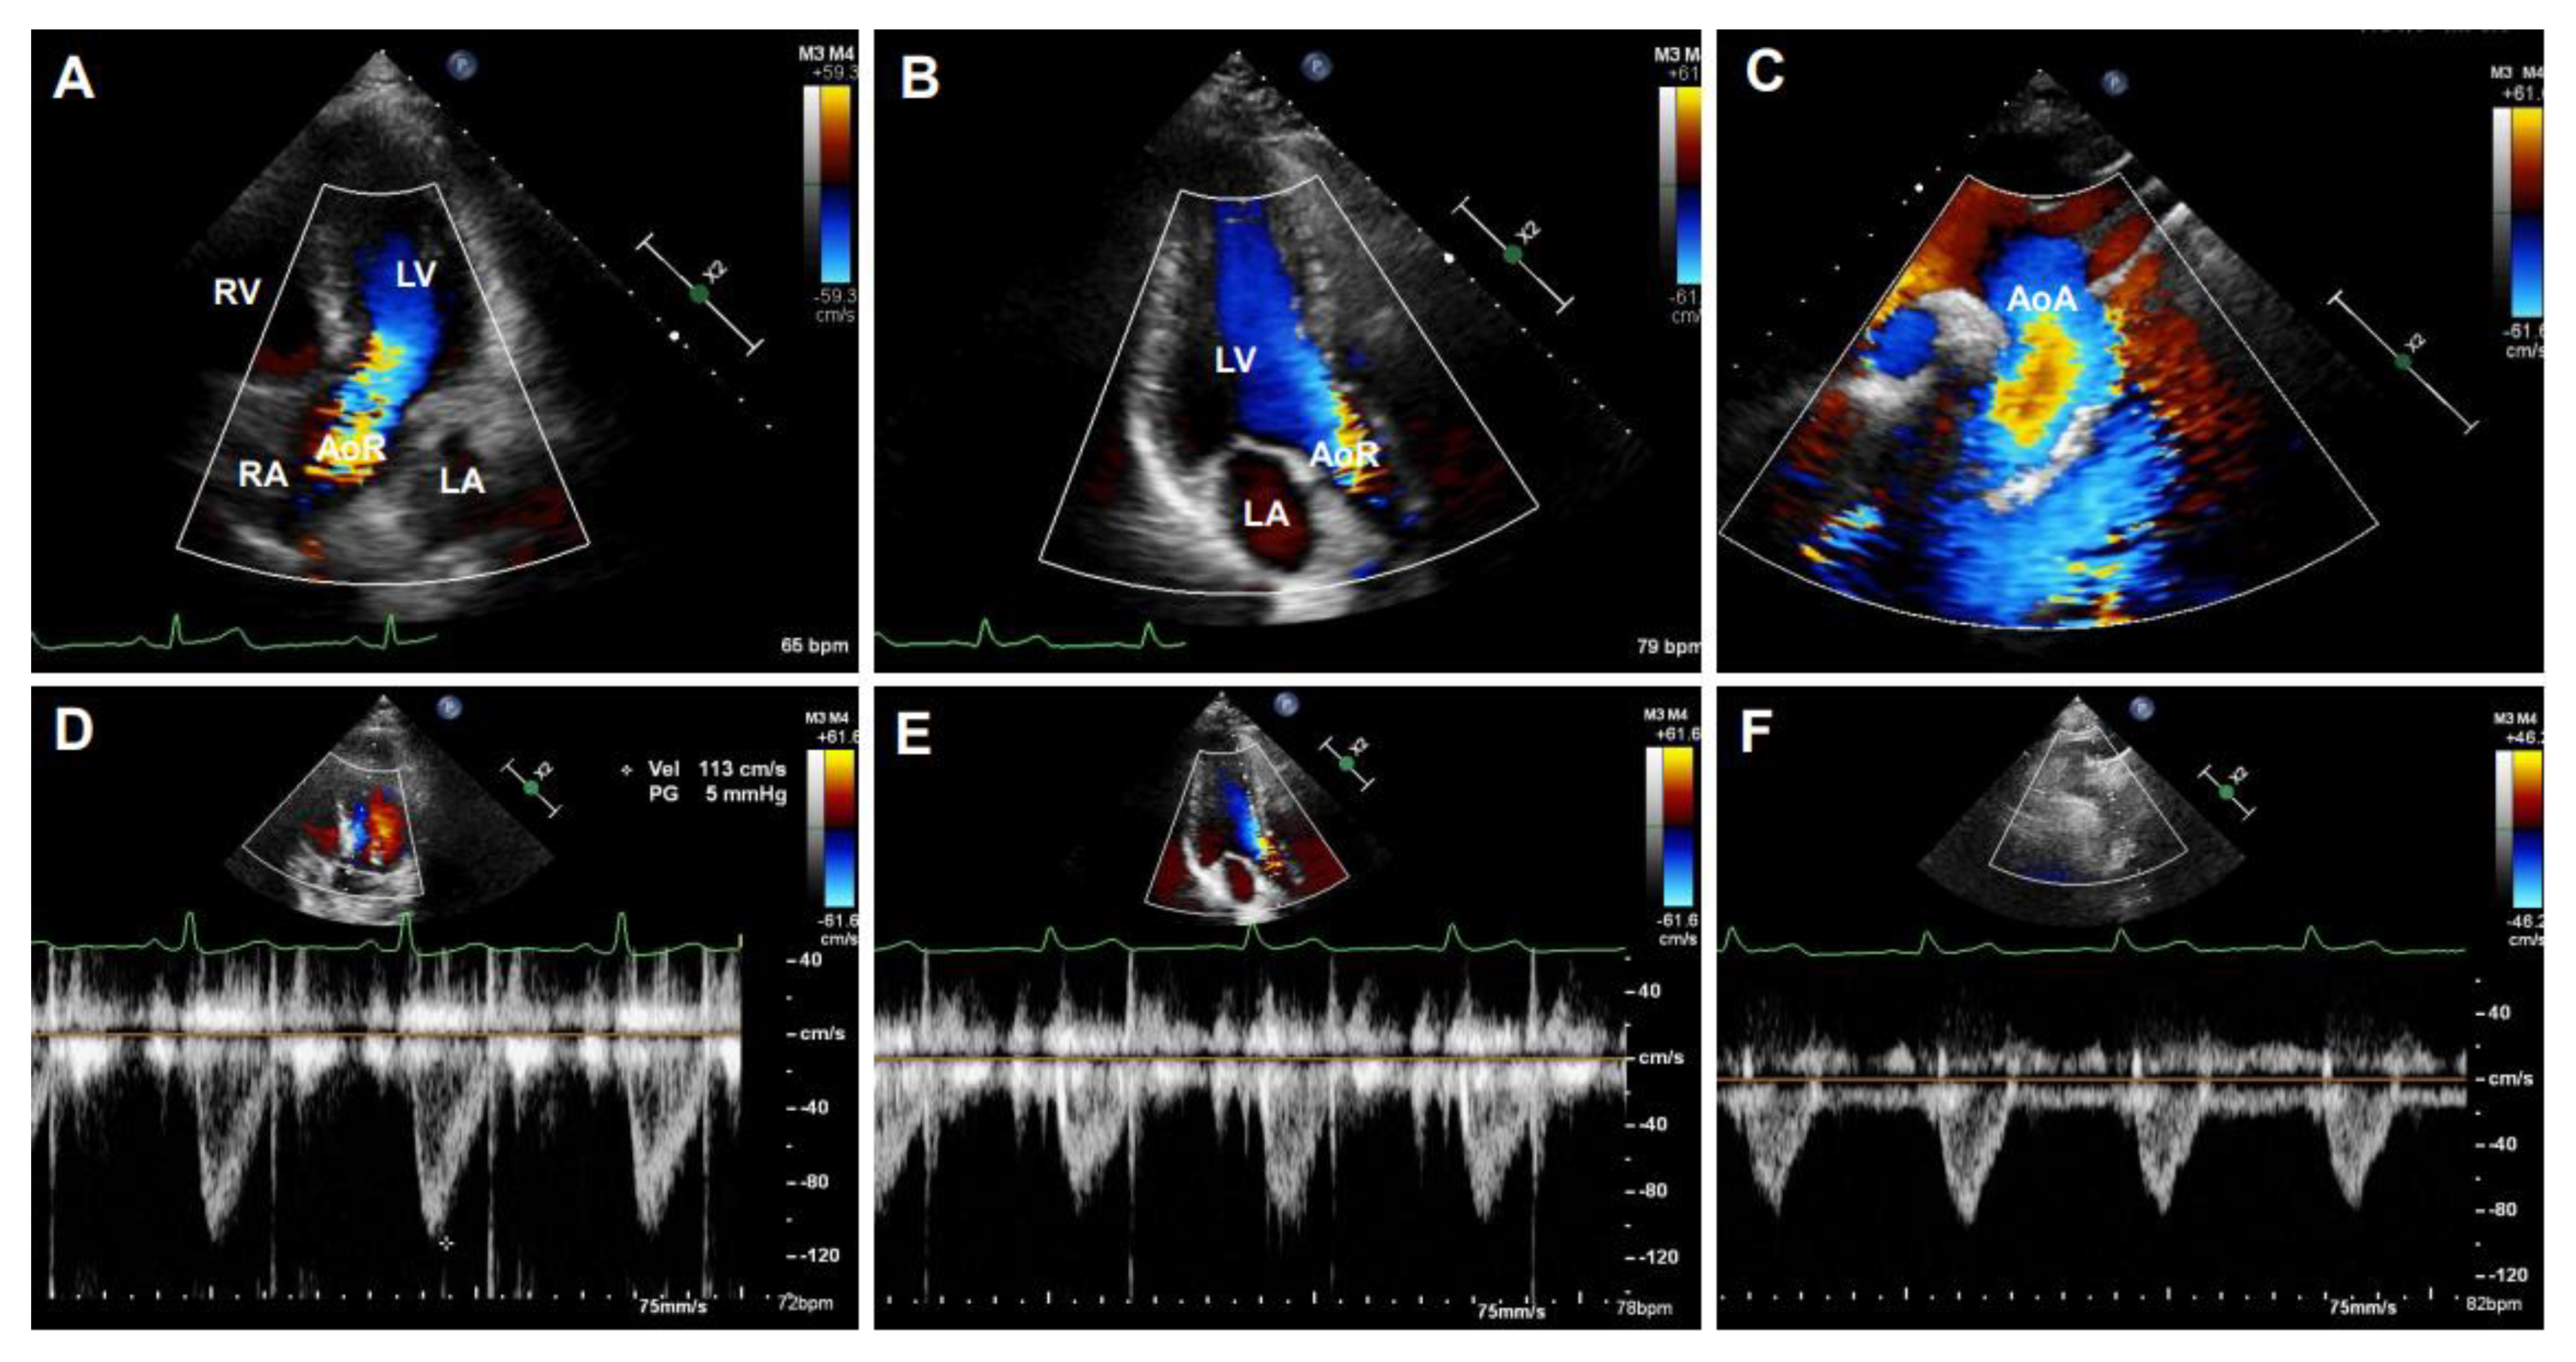

B-mode ultrasonography, also known as two-dimensional (2D) ultrasonography, is one of the most basic ultrasound models that produces a real-time black/white image of the targeted site, where the aortic wall is shown as echo-reflecting and the lumen as echo-free. As shown in Figure 3, the ultrasonographic view of the aorta is either circular in the perpendicular sections or tube-shaped in the parallel sections in humans. For example, the AoR and the AAo could be visualized in the parasternal long-axis view (Figure 3A), the modified right parasternal long-axis view, modified apical five-chamber (Figure 3B), and three-chamber views (Figure 3C). Additionally, the suprasternal view is a crucial view to visualize the AoA and the three supra-aortic trunks (innominate, left carotid, and left subclavian arteries), and a variable tract of the AAo and the DTAo (Figure 3D). In some cases, the entire arch could not be visualized in a single image plane because of the aorta’s extreme tortuosity. The DTAo can also be displayed in the posterior field through the cardiac acoustic window (Figure 3E). Moreover, parts of the DTAo may be invisible due to the tracheal air. The subcostal views may be helpful and allow the DAAo to be visualized (Figure 3F). Although B-mode has been widely used in humans, its application in mouse aorta remains relatively challenging, primarily because of the difficulty in obtaining exceptional spatial and temporal resolution in a small, rapidly varying vessel. Since apical views of the heart are prone to change in rodents, particularly in mice, it is difficult to obtain stable images of the aorta in this view. Reciprocally, the parasternal (Figure 4A), suprasternal (Figure 4B), subcostal, and transabdominal views (Figure 4C) are the most critical views for murine aorta, which enable an adequate assessment of the AoR, the AAo, and most of the segments of the DTAo and DAAo in mouse models.

Figure 4. B-mode imaged segments of a mouse aorta. (A): The parasternal long-axis view of the aortic root (AoR) and the ascending aorta (AAo). (B): The suprasternal view of the aortic arch (AoA). (C): The subcostal view of the descending abdominal aorta (DAAo). LV: left ventricle.

Diagnostics 11 00454 g004